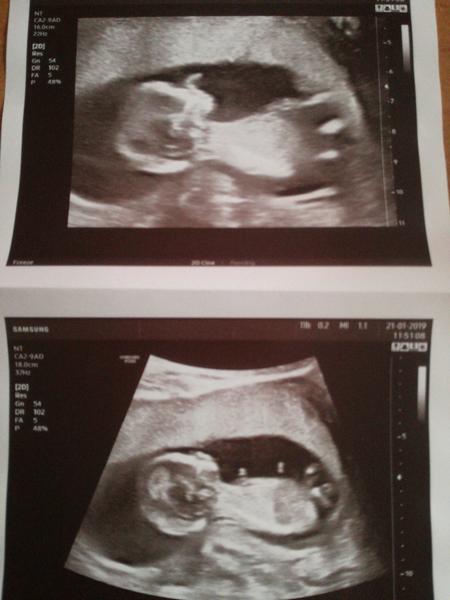

Je běžné, že na UZ v 11 týdnu nevidím končetiny? A kde najdu placentu?

1)Kde na obrázku mohu spatřit placentu ?

2)Je běžné že v 11 tydnu nevidím končetiny?

2) všem kdo slušně odpověděli děkuji , stejně mi nikdo ovšem nepotvrdil úplně moji domněnku , že placenta je tedy to s těmi dvěma ,,camprliky " vlevo , ale přesto děkuji za slušnou komunikaci .Je to zázrak v zaprděné komunitě , kde jsem nová.

@novamamina přečti si můj dotaz a tam odpověď najdeš , proč mě to zajímá ... Končetiny má , ale kde sem neviděla ..

Přikládám naší fotečku, kde vypadá jako s chobotem a pahýlkama, ale je to naprosto standardní mimčo 😀